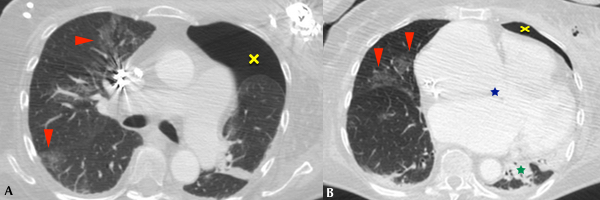

Se realizó TC de tórax a 85 (5,9%) pacientes, de los cuales 11 (13%) fueron positivos por PCR para COVID19. De estos, 9 (81%) manifestaron infiltrados en vidrio esmerilado en el parénquima pulmonar, asociándose además opacidades consolidativas en 4 (36%) de ellos (Figs. 3 y 4). 2 (18%) pacientes no mostraron afectación intersticio-alveolar en su evolución. La TC se realizó a pacientes cuya clínica no era acorde a los hallazgos de Rx y a aquellos con evolución tórpida (81%). En total, a 8 (72%) pacientes COVID-19 positivos se les realizaron ambos métodos imagenológicos.

En cuanto a la distribución, en los cortes axiales se encontró que siete pacientes presentaron opacidades o consolidaciones periféricas, o ambas (Figs. 5 y 6).

La cantidad de lóbulos afectados fue variable. Un paciente presentó afectación lobar única, uno afectación bilobar, cuatro afectación de tres lóbulos y dos pacientes de cuatro lóbulos. Únicamente un paciente sufrió compromiso panlobar (Fig. 7). Los lóbulos pulmonares con mayor afectación fueron los superiores: siete pacientes tuvieron afectación del lóbulo superior derecho y ocho pacientes del lóbulo superior izquierdo. Cabe mencionar, además, que ocho pacientes tuvieron afectación bilateral y uno unilateral.